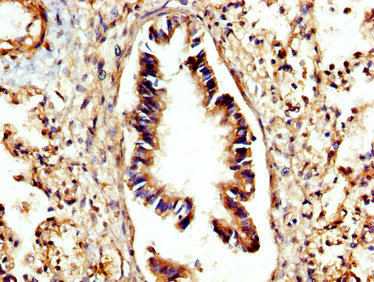

IHC image of CSB-PA006186LA01HU diluted at 1:300 and staining in paraffin-embedded human lung tissue performed on a Leica BondTM system. After dewaxing and hydration, antigen retrieval was mediated by high pressure in a citrate buffer (pH 6.0). Section was blocked with 10% normal goat serum 30min at RT. Then primary antibody (1% BSA) was incubated at 4°C overnight. The primary is detected by a biotinylated secondary antibody and visualized using an HRP conjugated SP system.